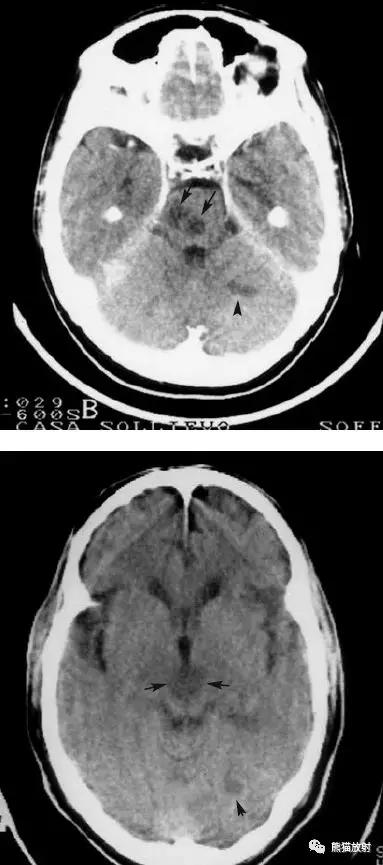

右侧大脑前、中、后动脉供血区巨大梗死

分水岭脑梗死(“Watershed” infarcts):右侧大脑前中动脉及中后动脉供血区之间梗死灶。

分水岭脑梗死:左侧深部和浅部大脑中动脉供血区之间梗死灶。

左侧尾状核头脑梗死;右侧外囊腔隙性脑梗死。

椎基底动脉区域的梗死:范围较广,非均质的低密度区域,累及脑干,小脑半球的前外侧以及颞叶的内后侧。

后颅窝梗死:脑桥、中脑、左小脑半球。

左侧及双侧丘脑梗死